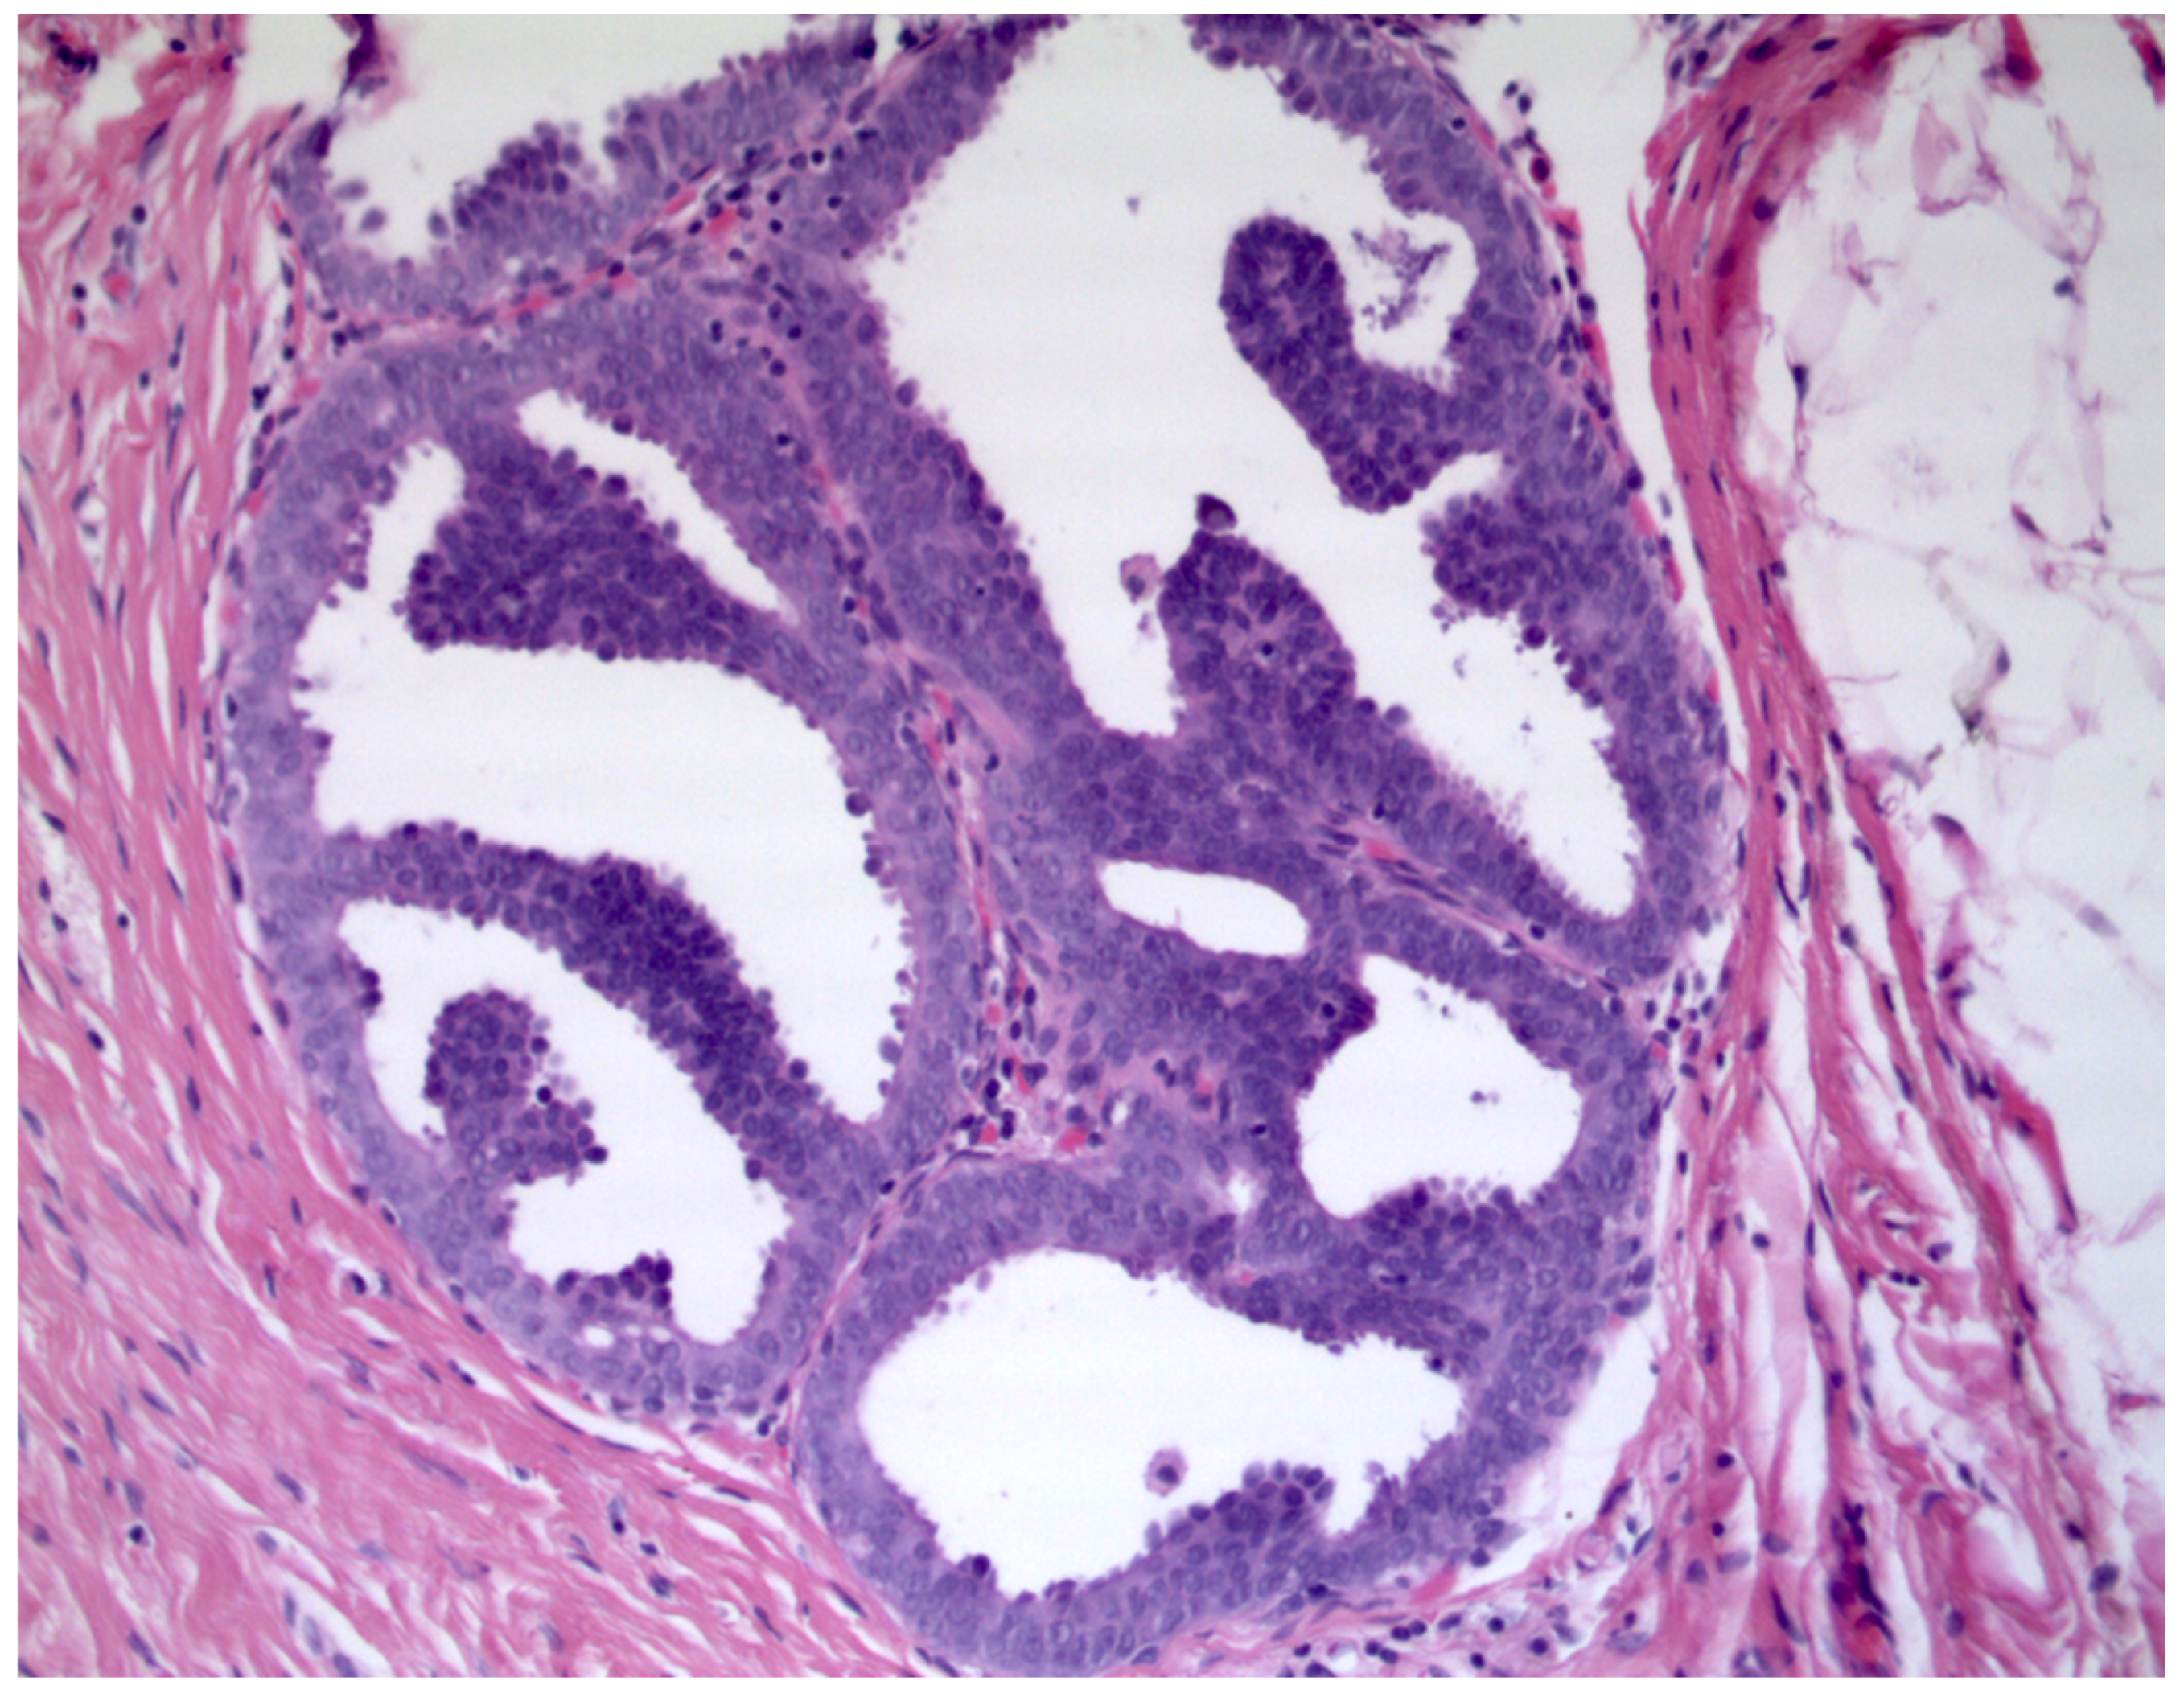

Breast lesions classified as having uncertain malignant potential (B3) on biopsy cause management challenges. Diagnostic improvement in the identification of breast lesions, together with the introduction of population-based mammographic screening programs, has led to an increased rate of B3 diagnoses. Atypical ductal hyperplasia (ADH) is one of the most frequent lesions observed. Mammographically detectable microcalcifications are typically associated [1]. ADH is morphologically defined as an epithelial intraductal proliferation with cytological and architectural features similar to those of low-grade ductal carcinoma in situ (DCIS), but with partial involvement of ducts and/or limited extension. ADH can exhibit different growth patterns (cribriform, micropapillary or solid) reaching up to 2 mm and is found in approximatively 1–10% of breast biopsies [1,2,3,4]. (Figure 1).

Figure 1.

Atypical ductal hyperplasia with cribriform and micropapillary growth pattern (Hematoxylin & Eosin, 400×).